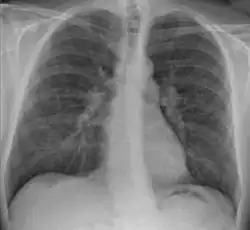

Chest X-ray showing the typical nodularity of sarcoidosis, predominantly in the hila of the lungs.

Chest radiograph changes are divided into four stages:[104]

1. bihilar lymphadenopathy

2. bihilar lymphadenopathy and reticulonodular infiltrates

3. bilateral pulmonary infiltrates

4. fibrocystic sarcoidosis typically with upward hilar retraction, cystic and bullous changes

Although people with stage 1 radiographs tend to have the acute or subacute, reversible form of the disease, those with stages 2 and 3 often have the chronic, progressive disease; these patterns do not represent consecutive "stages" of sarcoidosis. Thus, except for epidemiologic purposes, this categorization is mostly of historic interest.[28]